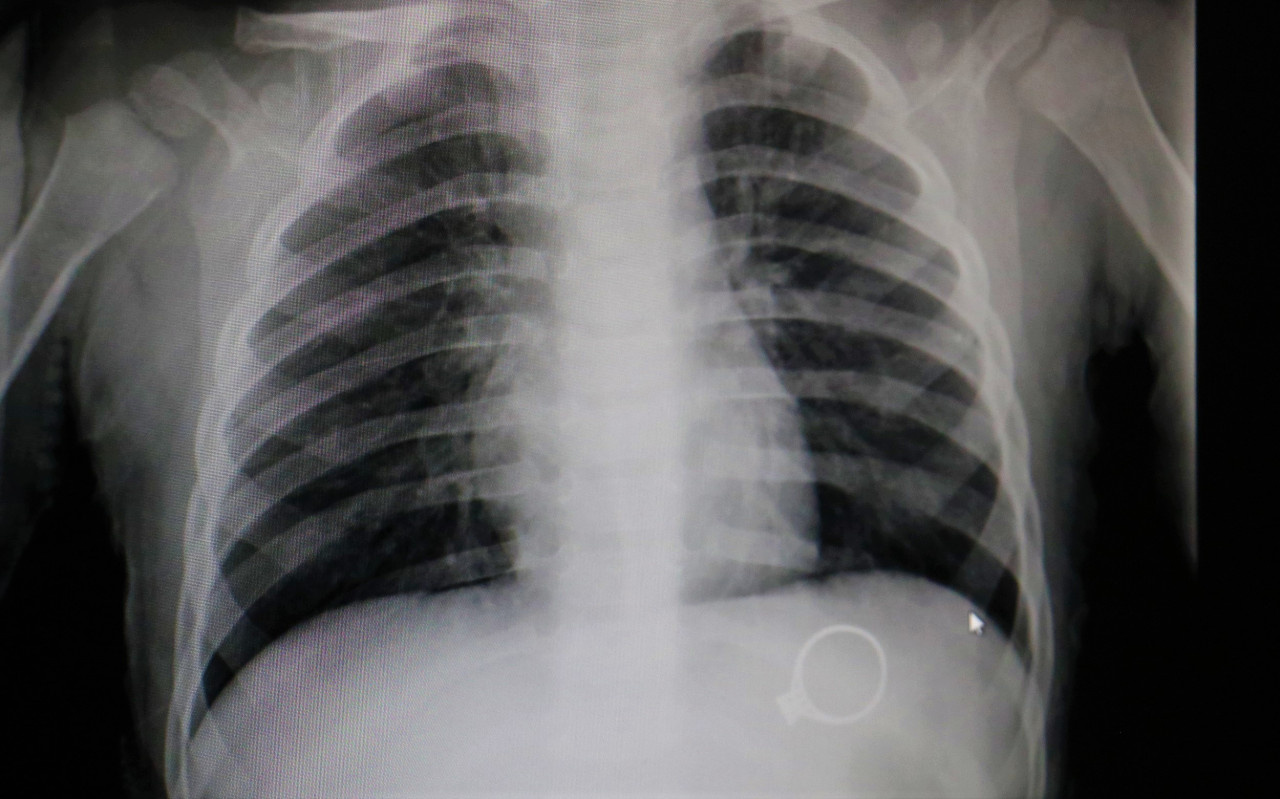

Kalp boyutu ve gölgesi, bazı kalp boşluklarındaki genişlemeler, akciğerin kanlanması ve damar gölgeleri, akciğer, omurga, göğüs kafesi kemikleri, karın içi.

Akciğer filmi iki yönlü olarak çekilir, akciğerler önden ve yandan çekilerek çevre organlarda ve göğüs boşluğunda oluşabilecek hastalıklara da tanı. 8 aylık bebeğime yabancı cisim yutma şüphesiyle röntgen çekildi röntgene baktığımda tüm vücudu çekilmiş zararı ne olur ne kadar etkilendi çok üzğünüm. Ürolitiyazis gibi tehlikeli bir hastalıktan şüpheleniliyorsa, çocuklar önce ultrason taraması için yönlendirilir.bununla birlikte, herhangi bir ultrason.

Genellikle rahim röntgeni (hsg) sonuçları, işlem bittikten sonra 10 ila 20 dakika sonrasında çıkar. Bebek için daha güvenli ve daha rahattır. Akciğer filmi iki yönlü olarak çekilir, akciğerler önden ve yandan çekilerek çevre organlarda ve göğüs boşluğunda oluşabilecek hastalıklara da tanı.

Sağlıklı bir hamilelik için gereksiz ilaç kullanımından uzak durmalı ve doktor önerisi olmadan hiçbir tedaviye başlamamalısınız. Hastaneye yatış bebeğin genel durumuna ve beslenmesine bağlıdır. Kalp boyutu ve gölgesi, bazı kalp boşluklarındaki genişlemeler, akciğerin kanlanması ve damar gölgeleri, akciğer, omurga, göğüs kafesi kemikleri, karın içi.

Akciğer filmi iki yönlü olarak çekilir, akciğerler önden ve yandan çekilerek çevre organlarda ve göğüs boşluğunda oluşabilecek hastalıklara da tanı. 8 aylık bebeğime yabancı cisim yutma şüphesiyle röntgen çekildi röntgene baktığımda tüm vücudu çekilmiş zararı ne olur ne kadar etkilendi çok üzğünüm. Hafta arasında yapılan tek seferlik röntgenler bebekler için herhangi bir sorun yaratmamaktadır.

Bebeğiniz nefes almakta veya beslenmekte güçlük çekiyorsa, hastaneye yatırılması gerekebilir. Kalp boyutu ve gölgesi, bazı kalp boşluklarındaki genişlemeler, akciğerin kanlanması ve damar gölgeleri, akciğer, omurga, göğüs kafesi kemikleri, karın içi. Gelişen teknoloji, döner aletler ve apex locator adı veriken kök ucu bulucu cihaz sayesinde, röntgen çekmeye gerek kalmadan gebelikte kanal tedavisi yapılabilir.

Tüm hastanelerde röntgen odasına hamileler giremez ibaresi koyulmaktadır. Tele (kalp röntgeni) kalp röntgeni (telekardiyogram = tele): Kalp boyutu ve gölgesi, bazı kalp boşluklarındaki genişlemeler, akciğerin kanlanması ve damar gölgeleri, akciğer, omurga, göğüs kafesi kemikleri, karın içi.